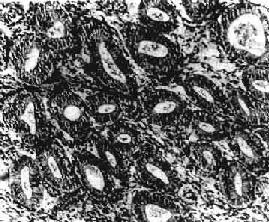

图13-6 子宫内膜增生症

腺体明显增多、大小不一、分布不均,腺上皮多层,间质增生,排列紧密

肉眼观,一般可见子宫内膜普遍增厚,可达0.5~1cm,表面光滑,柔软,也可呈不规则形或息肉状。镜下,可分4种类型:①单纯型,子宫内膜腺体及间质均增生,腺体明显增多、大小不一、分布不均(图13-6)。偶见腺体扩大成囊,腺上皮细胞呈柱状,缺乏分泌,往往排列成假复层。核分裂像常见。间质细胞排列紧密。②囊腺型,以增生腺体呈明显囊性扩张为特征。典型病例肉眼可见在增厚的内膜中有散在小孔形成,因此称之为瑞士干酪样增生。镜下,内膜腺体形状多样,大小极不一致,小者如增生早期的腺体,大者直径可为小的数倍至数十倍,大小腺体皆衬以假复层高柱状或立方上皮,并缺乏分泌现象。间质细胞丰富,胞浆少,核浓染。③腺样型,以腺体增生而密集排列和间质稀少为特征,腺体数量远比前两型为多,结构也更加复杂,腺上皮向腺腔内呈乳头状或向间质呈出芽样增生。间质稀少。腺上皮细胞为高柱状,假复层,核空泡状,核分裂像常见,但无明显异型性。④不典型增生,组织结构与腺样增生相似,腺体拥挤并呈不规则形、分支状或出芽样增生,间质明显减少,同时出现腺上皮细胞的异型性,细胞核大,染色质粗,核仁明显,上皮复层,失去极性,常见核分裂像。子宫内膜不典型增生有时很难与高分化腺鉴别,主要鉴别点是前者不见间质浸润。有人认为它是子宫内膜腺前变化。